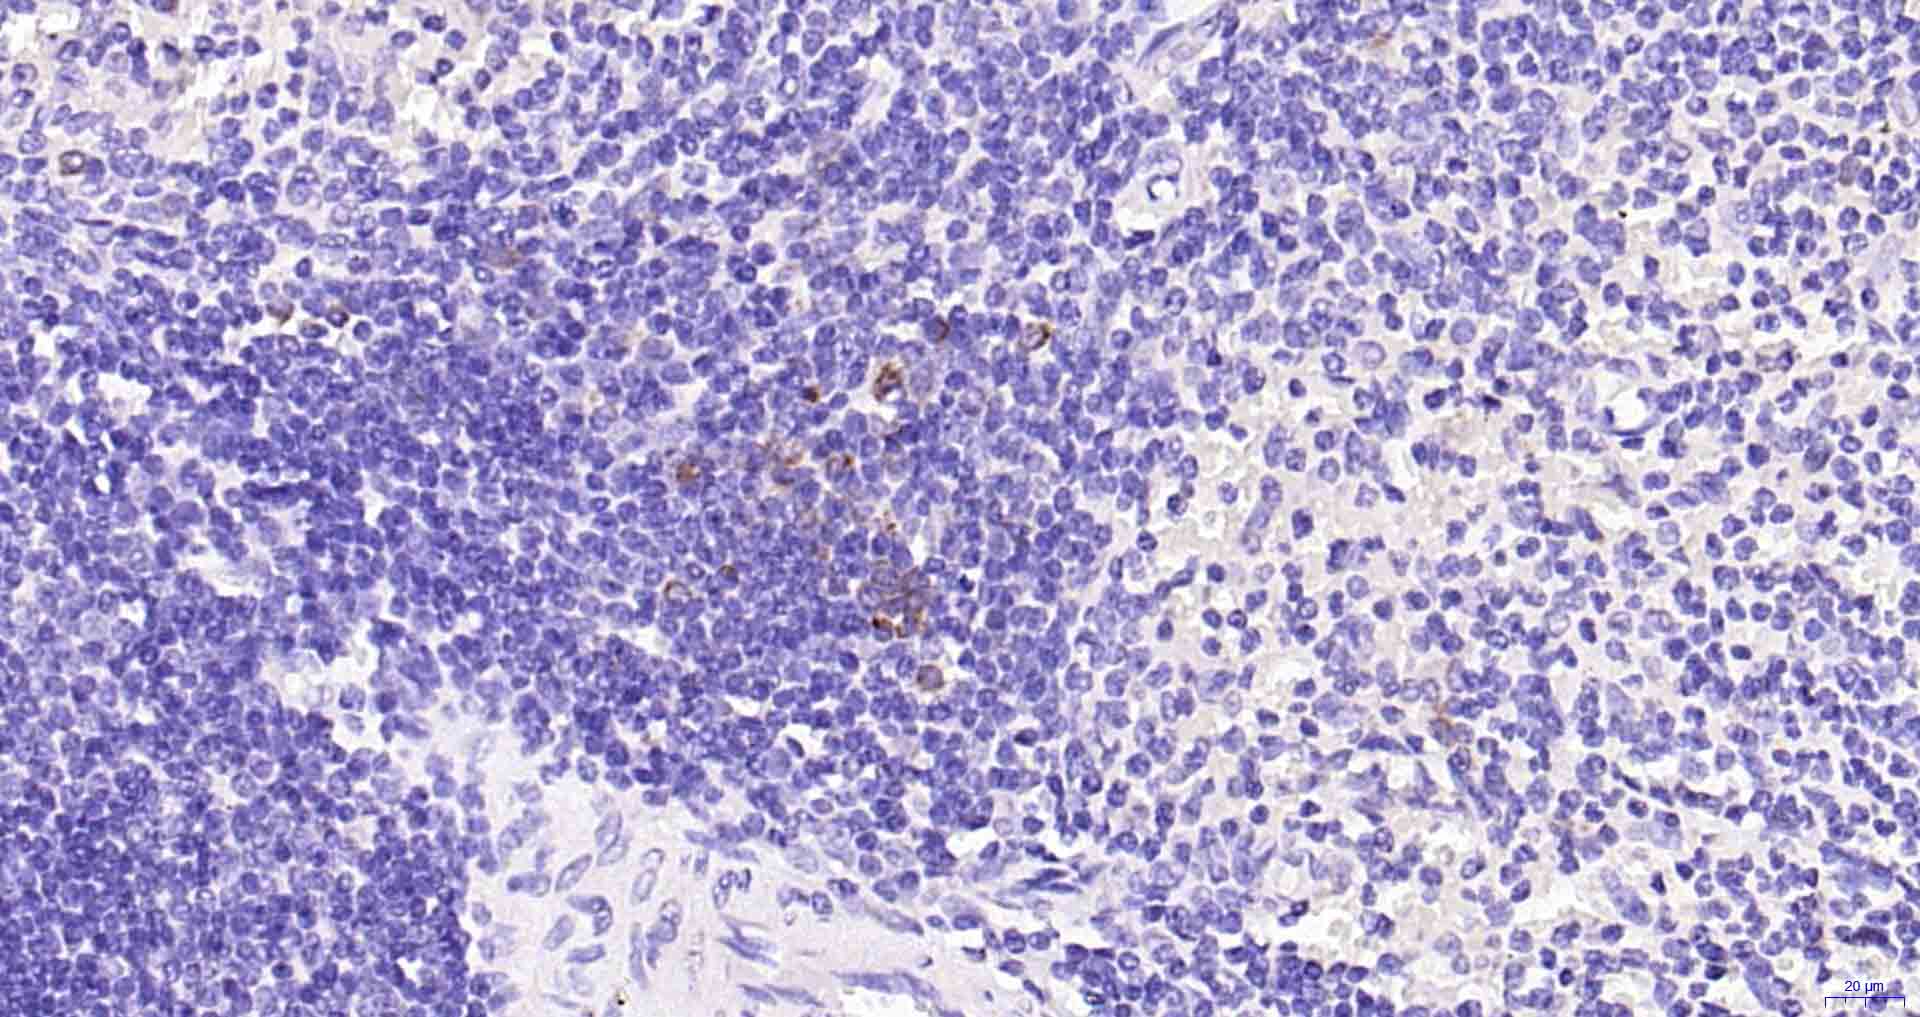

Paraformaldehyde-fixed, paraffin embedded Human Spleen; Antigen retrieval by boiling in sodium citrate buffer (pH6.0) for 15 min; Antibody incubation with Granzyme B Monoclonal Antibody, Unconjugated(bsm-60779R) at 1:300 overnight at 4°C, followed by conjugation to the SP Kit (Rabbit, SP-0023) and DAB (C-0010) staining.